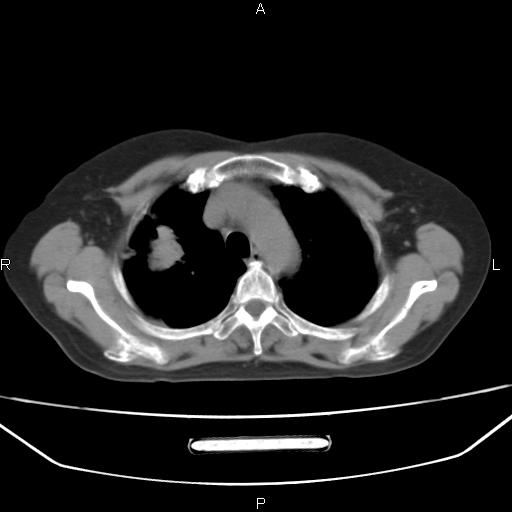

患者,女,66岁。健康体检胸部透视发现右上肺片状阴影。既往无不适,患者自诉三个月前曾有低热病史体温37.5左右一周。用药后缓解。至今无其它不适。请老师们指导指导。

考虑:右肺上叶周围型肺癌(分叶状肿块+砂粒状钙化+胸膜尾征)。

典型的中心型肺癌,尖段支气管阻塞。

周围性肺癌可能性大,建议增强